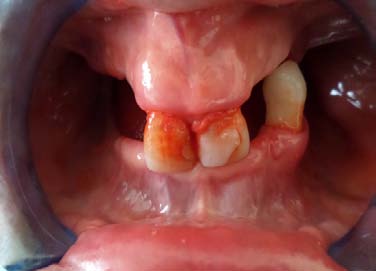

After 7 days the intracanal dressing was changed for another obtaining by mixing calcium hydroxide powder and tooth was sealed. On third visit the intracanal dressing was removed and the canal was irrigated with 17% EDTA and master cone radiograph was taken (figure 7). 21 was obturated with the lateral cold compaction technique and the portion of the canal below the resorptive defect was obturated with gutta percha (Dentsply, Maillefier Germany) and A H plus sealer (Dentsply, Maillefier Germany) using sectional condensation technique and the remaining canal was obturated with thermoplastized gutta percha technique. Then final restoration with composite was done followed with prosthesis (figure 8). In 21 root canal treatment was started with straight line access, working length was determined using radiograph(figure 10) and bleeding point was check using paper point. Biomechanical was done till 80K stainless steel file under copious irrigation with saline. Calcium hydroxide intracanal medicament was place for 2 week and cavity was sealed with temporary material. Following copious irrigation with 5% sodium hypochlorite, calcium hydroxide powder mix was renewed after a week.

Calcium hydroxide was renewed two times in 2 mon due to the exudation into the canal. At the 3 mon visit, white MTA (ProRoot MTA, Dentsply, TN, US) was prepared according to the manufacturer's recommendations and filled incrementally to the canal orifice with vertical condensation using the pluggers. Intraoperative radiographies revealed that MTA filled the canal and the resorption defect. A wet cotton pellet was put on the MTA, and the cavity was sealed with the temporary restorative material. After 7 days, the cavity was restored using a composite resin (figure11) filling (Supreme, 3M ESPE, Dental Products, MN, USA) and PFM crown was placed.